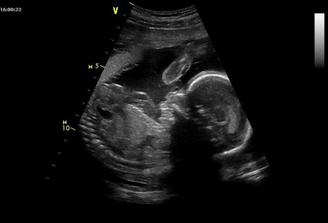

Od 14. května jsem doma na mateřské. Rychle to utíká. Vypadá to, že jsme oba zdraví a je vše v pořádku. Jen máme slabší krevní obraz a syndrom neklidných nohou, takže baštíme železo. Bříško hezky roste. Mimčo už umí double kopy do žaludku a žeber najednou a někdy i triple - do močáku 🙂. Máme za sebou předporodní kurz a ještě nás čeká kurz na kojení a péči o mimi..skoro všechny věci už máme koupené.